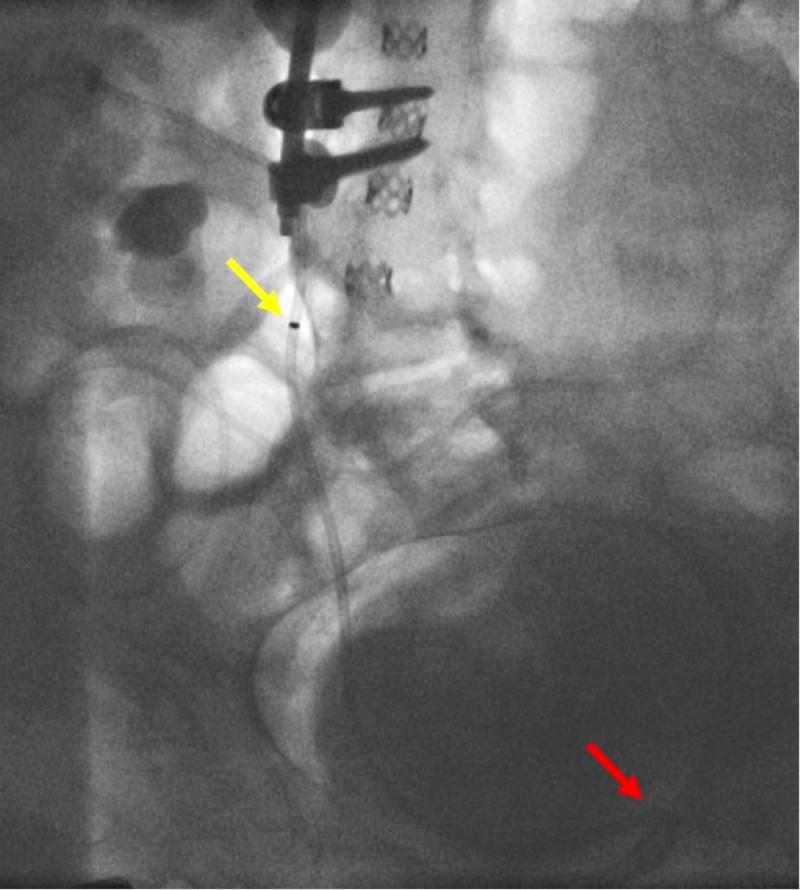

The percutaneous nephrostomy (PCN) is a relatively common interventional procedure used to treat a multitude of nephro-urological conditions. Traditionally, interventional radiologists use ultrasound guidance, needles, catheters, and guidewires to access the collecting system percutaneously. The placement of a nephro-ureterostomy stent may be precluded by challenging renal calyx anatomy or an underlying disease process that obstructs placement. In cases of complex obstruction, accessing the renal collecting system may require deviation from conventional methods. We present a case that after many failed attempts with a wide variety of guidewires and catheters, a steerable microcatheter (SMC) was used to safely and effectively access the renal collecting system. This novel technique utilizes the SMC to efficiently achieve complicated PCN stent placement, relieving the renal drainage system obstruction and potentially minimizing or avoiding complications, such as urosepsis and/or renal failure.

经皮肾造瘘术(PCN)是一种相对常见的介入手术,用于治疗多种肾泌尿系统疾病。传统上,介入放射科医生使用超声引导、穿刺针、导管和导丝经皮进入集合系统。肾输尿管造口支架的放置可能会因具有挑战性的肾盏解剖结构或妨碍放置的潜在疾病过程而受到阻碍。在复杂梗阻的情况下,进入肾集合系统可能需要偏离传统方法。我们报告一例病例,在使用各种导丝和导管多次尝试失败后,使用了可操纵微导管(SMC)安全有效地进入肾集合系统。这项新技术利用SMC有效地完成复杂的PCN支架置入,缓解肾引流系统梗阻,并可能将诸如尿脓毒症和/或肾衰竭等并发症降至最低或避免并发症的发生。